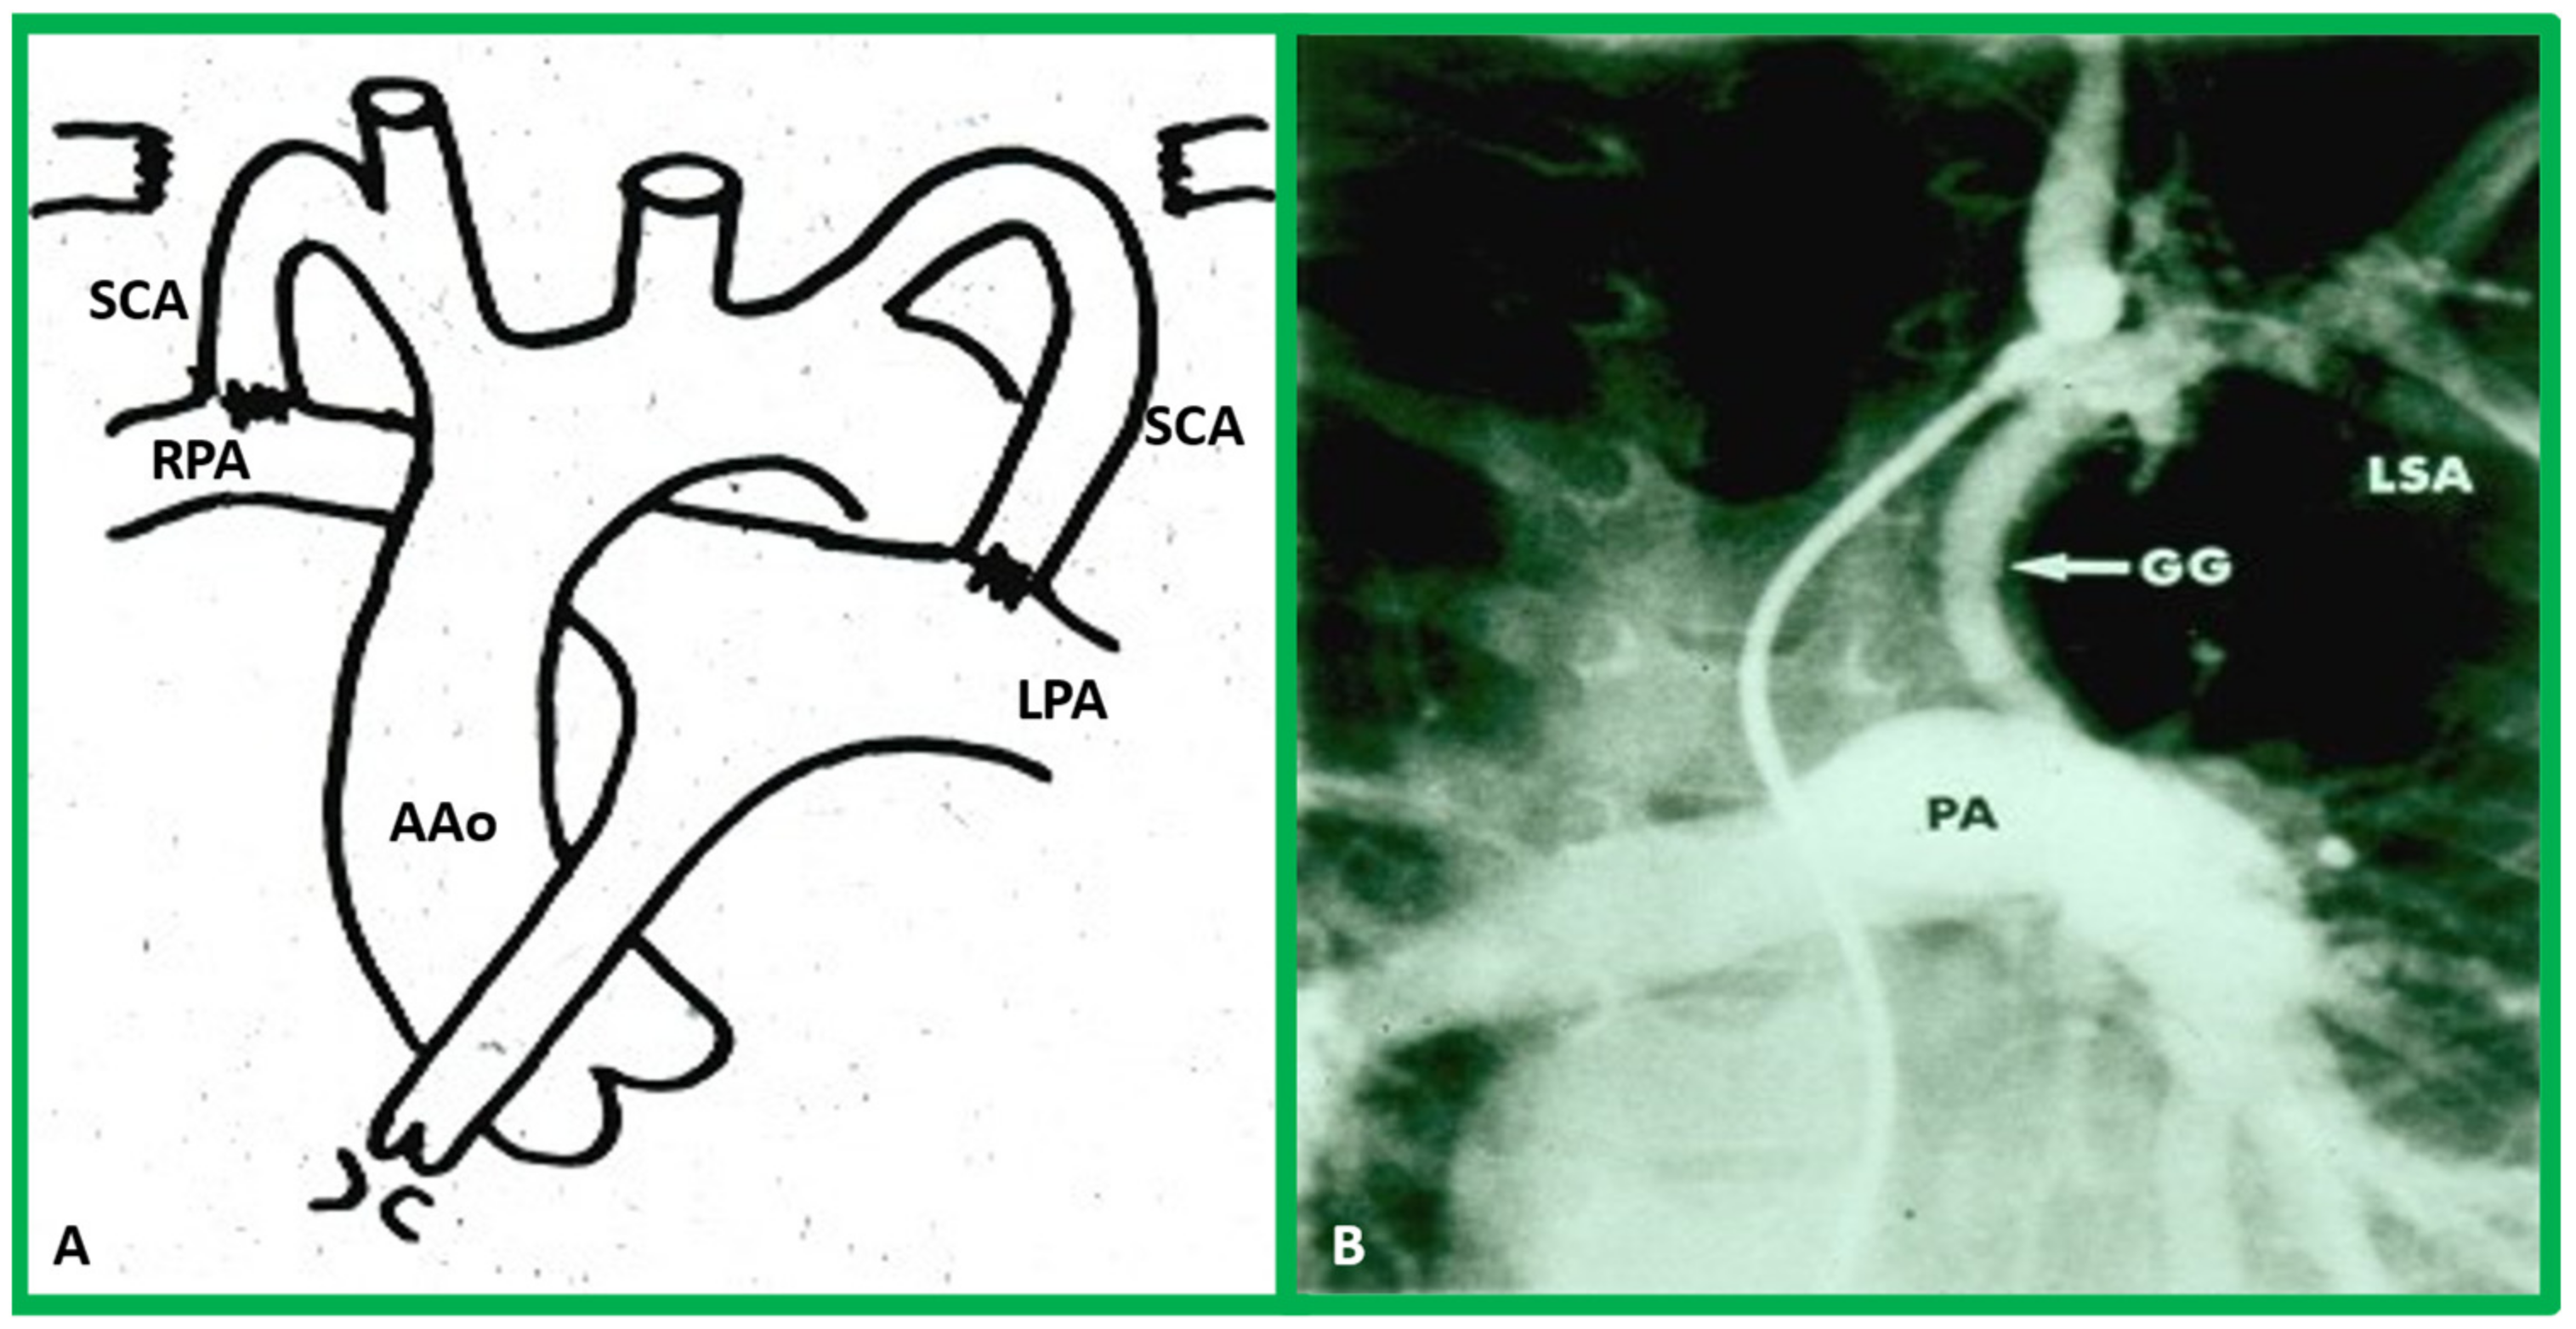

10.1.1. Reduced Pulmonary Blood Flow

10.2. Stage II